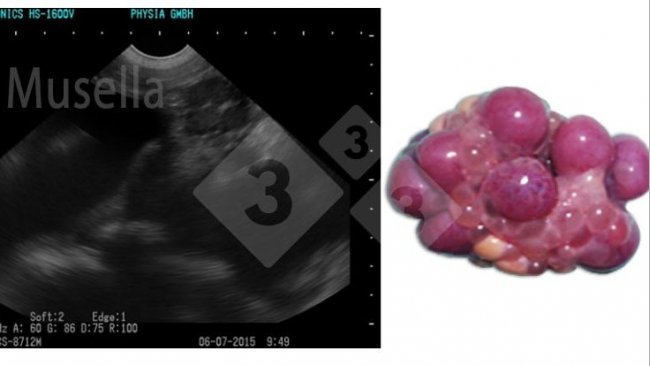

Quanto às novas técnicas com aparelhos de ultrassom de alta definição, capazes de identificar o estágio do ciclo da porca (a inseminação pode ser realizada pouco antes ou na ovulação), cientificamente são métodos de grande valor, mas com importante necessidade de qualificação do funcionário que o realiza e um alto nível de disponibilidade de pessoal, uma vez que o acompanhamento do crescimento folicular e, portanto, do momento do ciclo estral, requer várias observações por dia, o que dificulta sua implantação na granja.